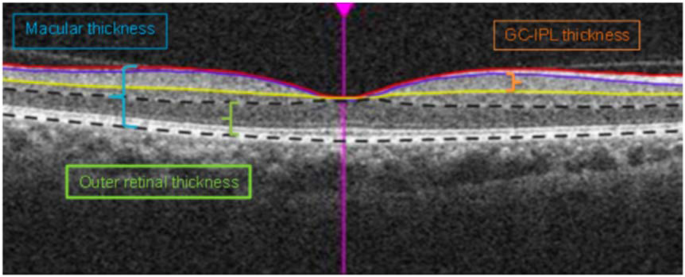

Cirrus High-Definition OCT (HD-OCT, Carl Zeiss Meditec, Dublin, California, USA) was used to capture images of the macula following pupil dilation. In each study eye, a macular cube scan of 6 × 6 mm2 area centred on the fovea was acquired based on the 512 × 128 protocol and automatically analysed by the Cirrus HD-OCT software V6.5. The macula is subdivided into nine macular subfields as defined by the Early Treatment Diabetic Retinopathy Study (ETDRS) with the foveal central subfield defined as central 1 mm diameter, and the inner ring and outer ring with diameters of 3 mm and 6 mm, respectively. Both inner and outer rings are further divided into superior, inferior, nasal and temporal quadrants. The average overall macular thickness was measured from the internal limiting membrane to the retinal pigment epithelium (RPE) of the macular cube. The average ganglion cell-inner plexiform layer (GCIPL) thickness and outer retinal thickness were measured across an elliptical annulus within the 6 × 6 mm2 area. GCIPL was segmented from the outer boundaries of retinal nerve fibre layer to the inner plexiform layer, and outer retinal layer was segmented from the outer plexiform layer to the RPE layer (Fig. 1). The four main exposure variables evaluated were foveal central subfield thickness, average macular thickness, average GCIPL thickness, and average outer retinal thickness.